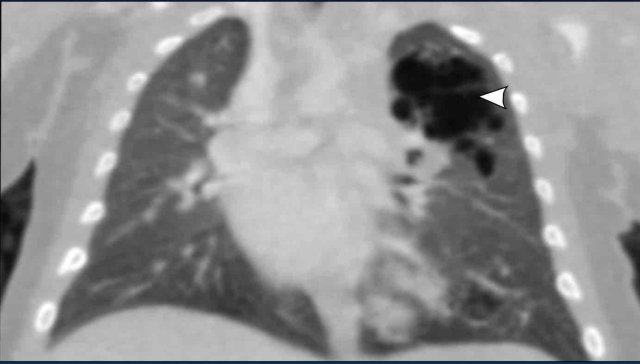

Image

CT scan of the same patient as above.

The lucent lesion in the left upper lobe has a multicystic aspect.

Because the largest cyst has a diameter of more than 2 cm, this is classified as a type I CPAM.